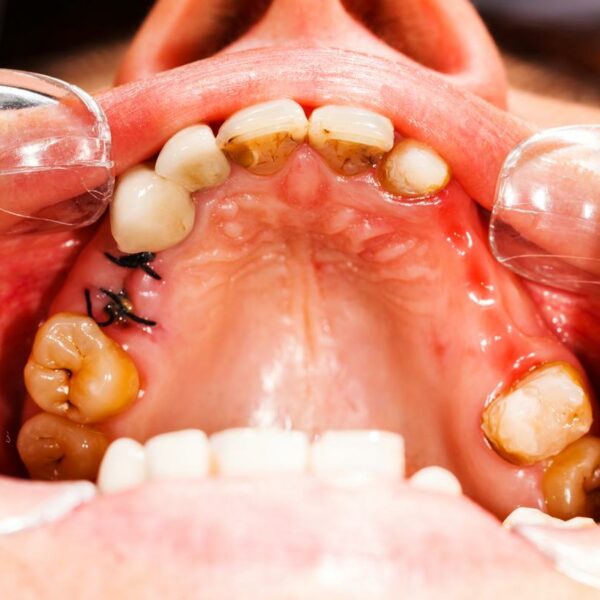

Caries, the other word for cavities, can be defined as the small holes or openings in the teeth that are a result of decaying tooth. To be able to know as to how to treat cavities, first, it’s important to know the causes of cavities. Cavities are a result of plaque and bacteria that builds its home on the teeth’s surface. Also, one who does not follow a good dental hygiene and does not have enough minerals in the diet is prone to having cavities in their teeth.

- Dark-stained pits and holes on the tooth/teeth.

- Breaking or chipping of the teeth, thus exposing a black inner surface.

There are some cavities, not visible to the naked eye that reside at the back of the mouth or between teeth. Now these cavities, although, don’t cause pain, can be identified only through ultrasound, x-rays, and/or fluorescent lighting. Therefore, it is extremely important to see your dentist regularly in order to keep your teeth in good health.